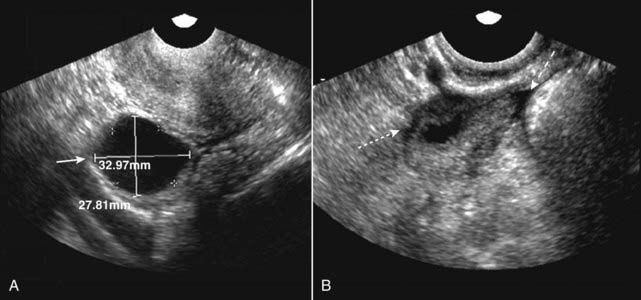

Figure 19-17 Dominant follicle ruptures during scan.

Under normal hormonal stimulation, one egg-containing follicle becomes dominant and attains a size of about 2.5 cm at the time of ovulation. A, The dominant follicle is 3.3 × 2.8 cm at the start of the study (solid white arrow). B, A few minutes later, during the study, the follicle ruptures (ovulation occurs) and the follicle shrinks dramatically in size (dotted white arrow). A small, physiologic amount of free fluid appears in the peritoneal cavity (dashed white arrow).